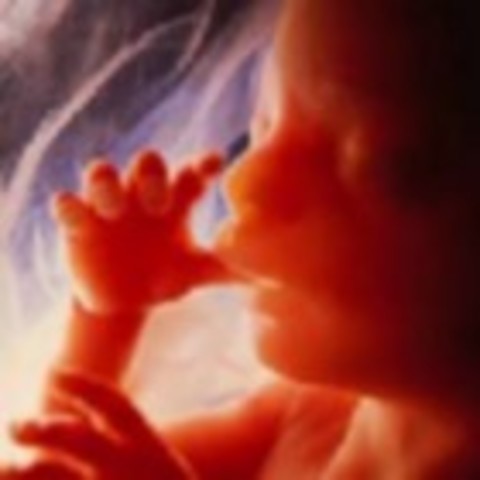

The child can successfully suck. Bones located in the middle ear harden.

The eyelids can be seen very clearly. If born at this stage is officially considered viable, they may well be able to survive.

Bones are becoming solid, hands are now fully developed. The brain is growing rapidly, the brain cells are starting to mature. The sexual organs are fully developed.